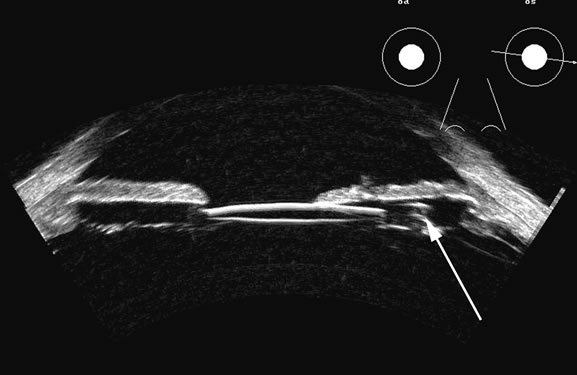

Vitreous foreign bodies are typically metal or glass objects, or intraocular lens implants. The ultrasound examination, with its better spatial resolution, is best performed following radiographic or computed tomography examinations in order to identify the location and number of foreign bodies. Ultrasonography is used to relate the position of a foreign body to the retina and lens and identify coexisting structural changes, such as retinal detachment. Metal and glass “absorb” or, more correctly, deflect sound, so that an anechoic area appears posterior to the foreign body. This area can act as an acoustic “pointer” to the foreign body (Fig. 18). A-scan or gray scale on B-scan shows a highly reflective surface of the foreign body. BBs and shotgun pellets often create a “ringing” artifact that can also act as a pointer leading to the foreign body.19 The foreign body can be easily demonstrated by lowering the gain; the foreign body remains, whereas other, less reflective tissue planes fade away due to a lower difference in acoustic impedance between tissues than metallic or glass foreign bodies. Most foreign materials have a higher density than the vitreous, and sound that passes through the foreign body may appear to move the succeeding surface forward because of the faster sound transit.

Fig. 18. A foreign body localized in the iris is easily imaged with high frequency. Characteristic trailing multiple echoes always point to the location of the body itself (arrow).

Wood may be seen with ultrasound but is far less well differentiated than metal. Air bubbles are highly reflective and may resemble a metallic foreign body. An air tamponade of the vitreous compartment prevents acoustic viewing of the structures behind the bubble. A silicone-filled vitreous produces marked distortion of the globe behind the silicone, as well as marked attenuation (Fig. 19), since sound travels slower in silicone than saline; thus, the sound is deflected away, much as with a minus lens.20 Typical sound velocities in ocular tissues are shown in Table 1, in which velocities from several sources are compiled.21–24 Some disagreement on experimental data and methodology exists,25–27 but these values are generally accepted.